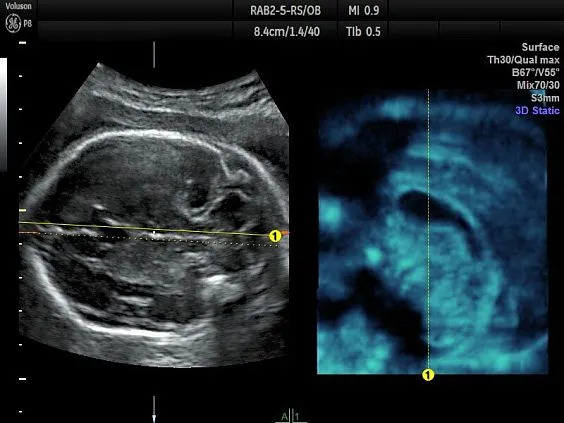

Клинические изображения

Несмотря на демократичную цену, Voluson P8 обеспечивает изображение экспертного уровня, включая поддержку 3D/4D-визуализации, что делает его востребованным в акушерстве и гинекологии. Он построен на платформе Voluson Core Architecture, которая гарантирует высокое качество двухмерной и трёхмерной визуализации, а также стабильную производительность при рутинных исследованиях.

- Программный пакет 3D/4D Activation:

- Режим 3D

- Режим 4D Realtime

- SonoRenderlive – автоматическое определение границ конечностей и лица плода и получение объемного изображения в 3D/4D

- RAB2-6-RS - датчик 4D конвексный 2-5 МГц для акушерско-гинекологических и абдоминальных исследований. Имеет уменьшенные эргономичные габариты и вес

Простота получения 3D-изображений

Визуализация в режимах 3D/4D позволяет исследовать дополнительные анатомические плоскости, повышая вашу уверенность в диагностике.

- Визуализация плоскостей недоступных для исследования при 2D-сканировании, для более точной диагностики.

- Просмотр и обработка объемных изображений в разных плоскостях или с использованием разных режимов сканирования.